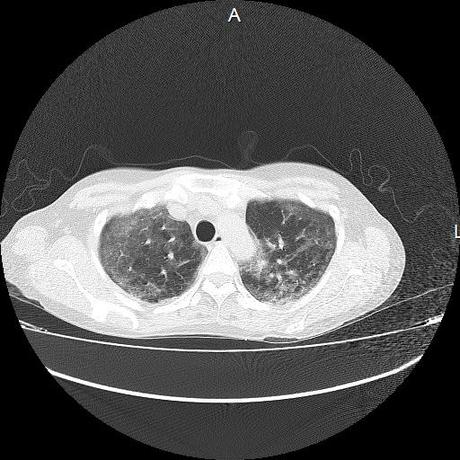

El parénquima pulmonar con areas parcheadas difusas en vidrio despulido combinadas con otras areas hipodensas de baja atenuación debidas a atrapamiento aéreo y engrosamiento intersticial y zonas de fibrosis de predominio en lóbulos medios e inferiores de ambos pulmones.

- LOS HALLAZGOS PUEDEN ESTAR EN RELACIÓN A NEUMOPATIA INTERSTICIAL PROBABLE ETIOLOGIA HIPERSENSITIVA VS AUTOINMUNE/BACTERIANA/FUNGICA.